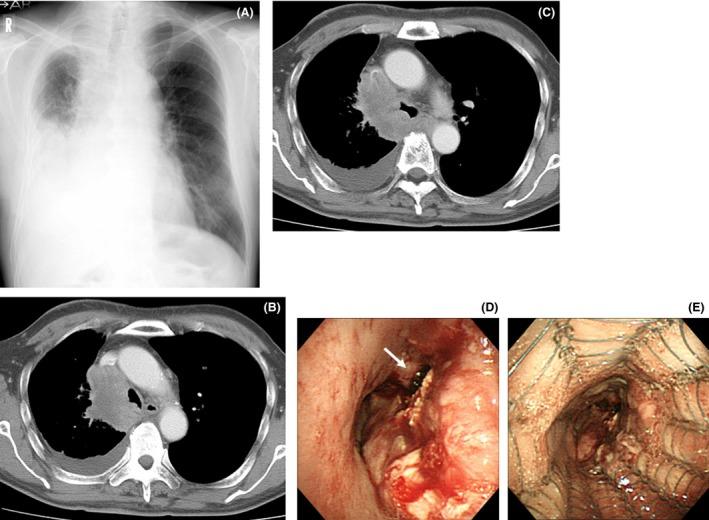

采用自膨式金属支架“并排”法并联合化疗成功治疗恶性隆突受累。

Successful management of malignant carinal involvement by "side-by-side" method of self-expandable metallic stents followed by chemotherapy.

Bilateral self-expandable metallic stents may be useful in the management of malignant carinal involvement and may improve the performance status of patients. This strategy may allow patients with poor performance status to receive additional chemotherapy.

摘要